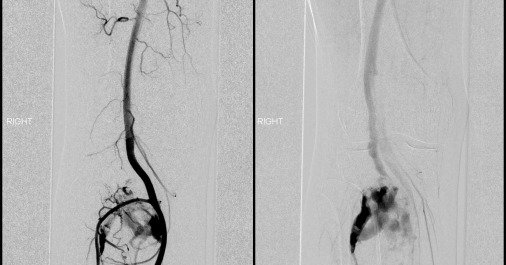

π©»β‘ When stents fail silently. This case reports a superficial femoral artery pseudoaneurysm from stent fracture noninfectious & atraumatic managed successfully with endovascular repair. π https://t.co/HCj8VrYqDC

Stent fractures of the peripheral arterial system are a documented phenomenon with the most common location being areas of high mobility such as behind the knee or groin. Concurrently, pseudoaneurysm...